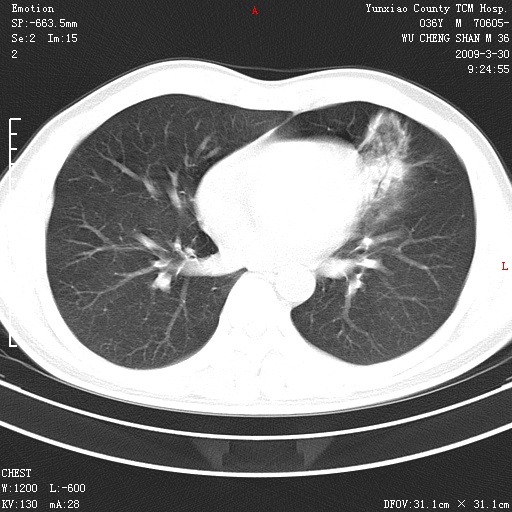

本院家属,胸痛,无咳嗽咳痰发烧病史,治疗一个月后病灶无明显改变,支气管镜示左肺慢性炎症,未见癌细胞,

胸痛,无咳嗽咳痰发烧病史,治疗一个月后病灶无明显改变,支气管镜示左肺慢性炎症,未见癌细胞,左肺下叶前段片状影,边缘不清,内见空支气管征,纵隔未见淋巴结肿大,周围无卫星灶,应考虑为炎性病变。

胸痛,无咳嗽咳痰发烧病史,治疗一个月后病灶无明显改变,支气管镜示左肺慢性炎症,未见癌细胞,左肺舌叶片状影,边缘不清,内见空支气管征,周围无卫星灶,应考虑为炎性病变。

左肺舌叶片状影,边缘不清,内见空支气管征,炎性病变